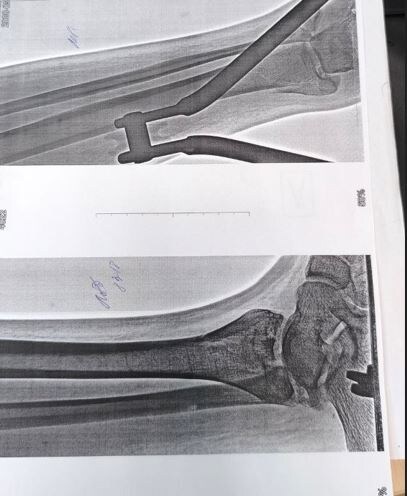

— "Мам, я сломал ногу". Дал трубку учителю ОБЖ, он спрашивает: "Мы вызываем скорую?". Я говорю: "Естественно, я сейчас приеду". Я была на работе, помчалась туда, на месте уже была скорая, ему ногу перебинтовывают. Спрашиваю: "Что случилось?" Упал с лестницы. Сразу поехали в 7-ю больницу, там сделали рентген, КТ, оказался очень сложный у него перелом, там несколько костей со смещением, осколками, надо собирать. Поставили ему костное вытяжение, провели через пяточную кость спицу, потому что в падении она как бы приплюснулась, — объяснила Екатерина.

Повторный рентген показал, что от процедуры есть положительный эффект. Однако ситуация осложнилась анамнезом мальчика. По словам Екатерины, сын с 4 лет болеет лейкозом, в 8 лет у мальчика был костно-мозговой рецидив, сейчас в стадии ремиссии. Матвей долго лечился и это могло повлиять на структуру костей, кроме того, к общей картине присоединилась инфекция. Сейчас школьнику колют антибиотики и из-за этого пришлось перенести операцию.